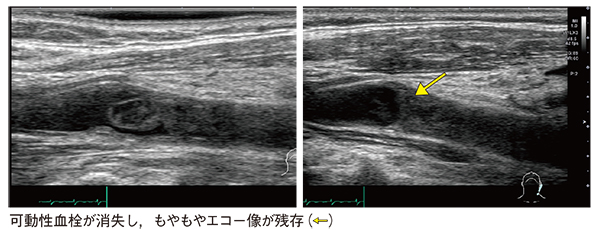

症例2は,90歳代,女性。右片麻痺,歩行困難で受診。脳梗塞と診断され,精査のため頸動脈エコーを行った。他社製装置では,頸動脈洞にプラークによる狭窄が認められ,一部が可動しているようにみえた。しかし同日,「Aplio i800」のPLI-705BXで撮像したところ,プラークではなく,可動性の血栓であると考えられた。これにより治療が大きく変更され,抗凝固薬の投与を開始したところ血栓が消失し,もやもやエコー像の残存が確認された(図3)。

図3 症例2:脳梗塞精査にてPLI-705BXにより治療が変更となった症例